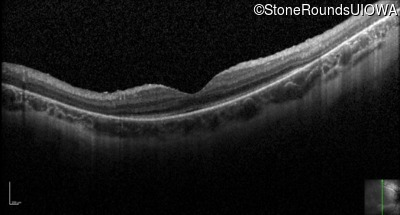

Optical Coherence Tomography - Left - 10/160 -1 sc

Exemplar / OCT Stack